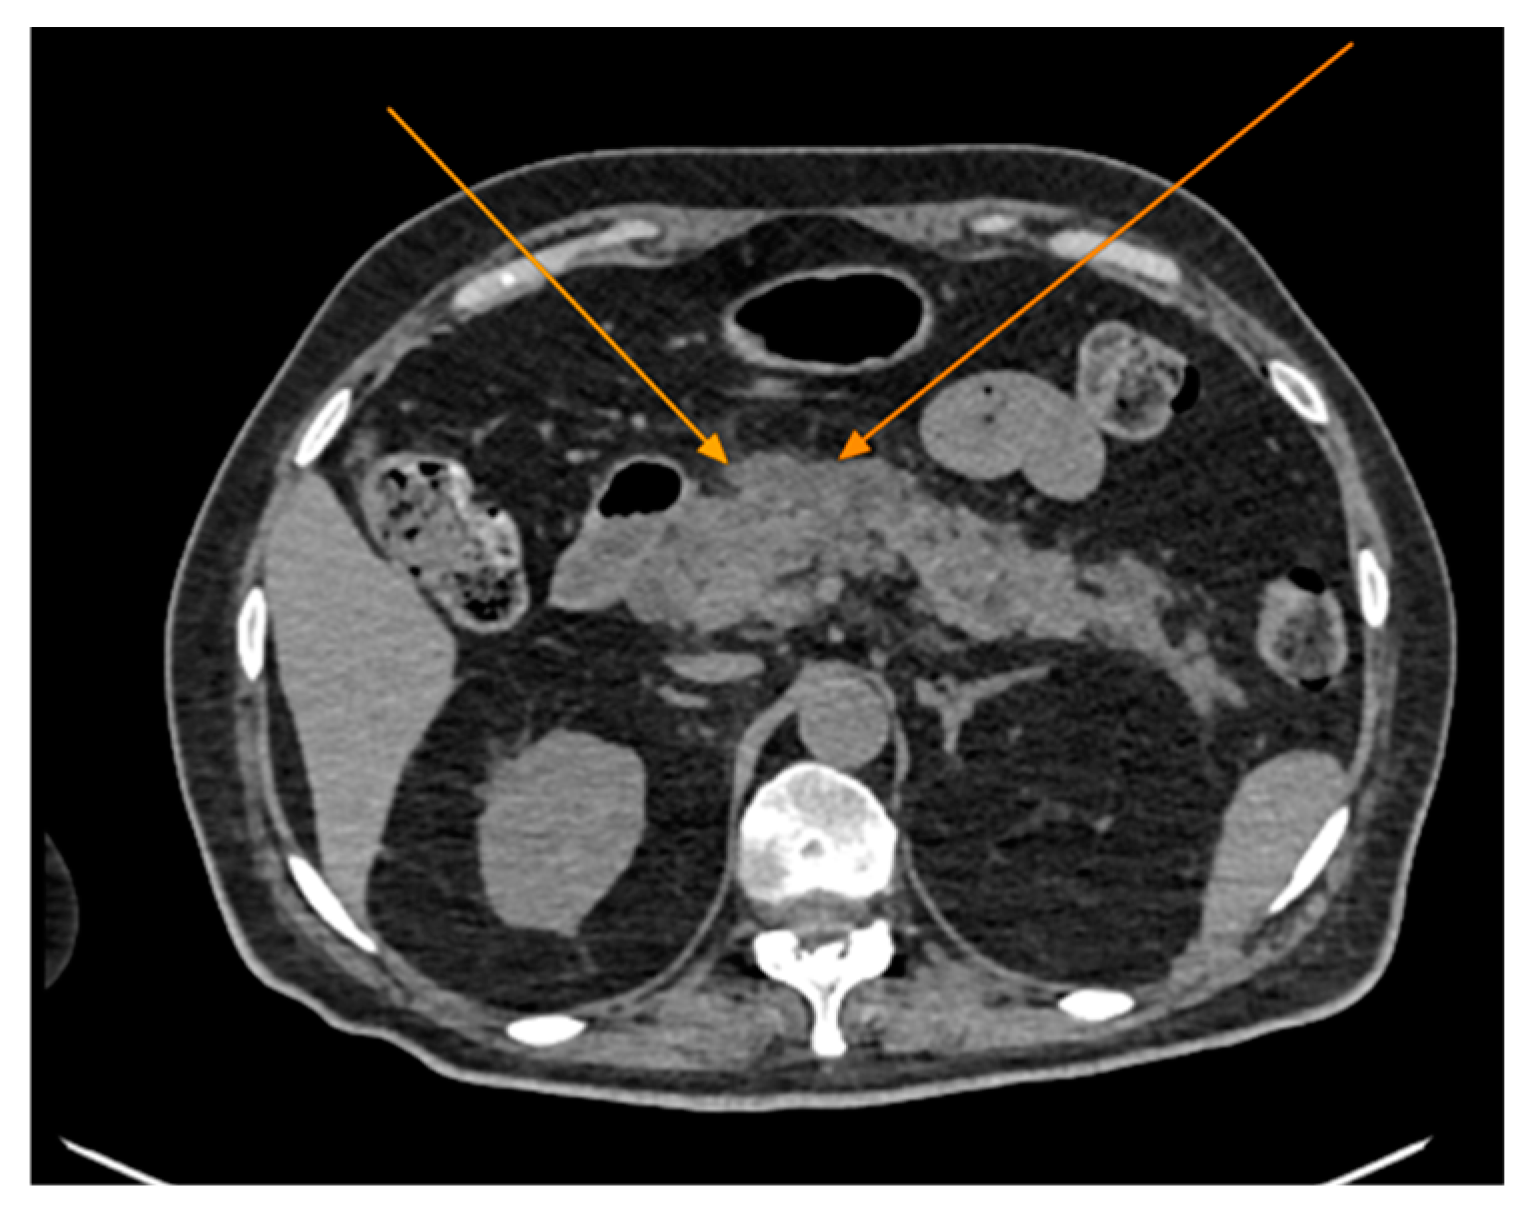

The chest CT scan performed in the emergency department (Figure 1) revealed the presence of pneumomediastinum. CT scans of the abdomen and pelvis were also performed, giving the high lipase and epigastric pain, revealing findings consistent with acute pancreatitis (with peripancreatic fluid collection, consistent with moderate acute pancreatitis per the modified CT severity index), as well as a solitary biliary stone measuring approximately 20 mm in diameter, without intra or extrahepatic biliary ducts enlargement (Figure 2).

Figure 2. Abdominal CT scan showing acute pancreatitis (arrows), axial view.